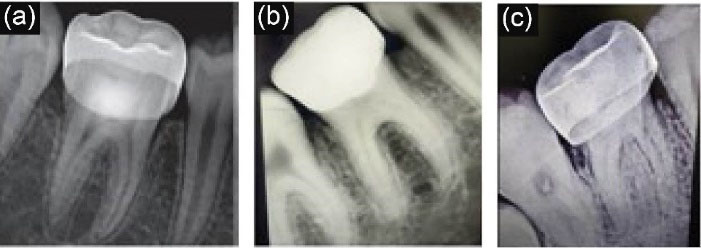

Radiographic assessments were carried out at 6-, 12-, and 24-month intervals (). At the 6-month recall, of the 45 patients, there was 100% radiographic success in terms of the integrity of lamina dura, furcal radiolucency, internal root resorption, external root resorption, and root canal obliteration. At the 12-month interval, of the 44 reporting patients, the success rate was 97.78% since there was one clinical failure at 9 months. Similar results were seen at the end of 24 months, as shown in Table 2.

joddd-16-264-g003

Figure 3. (a) 6 months follow up radiograph, (b) 12 months follow up radiograph and (c) 24 months follow up radiograph